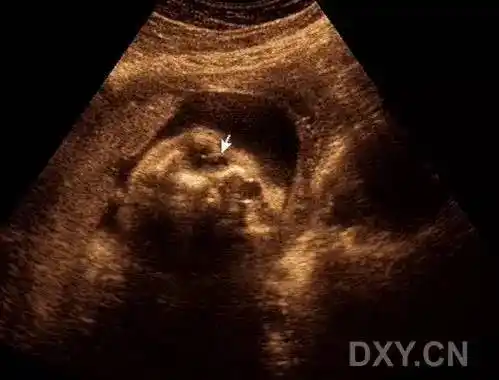

产前超声:泪囊囊肿与鼻泪管囊肿